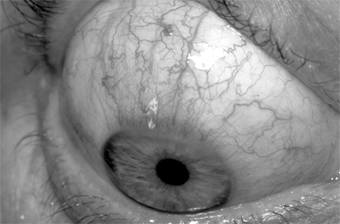

Microscopic examination of the nodules shows lymphocytes and epithelial cells. The peripheral cornea may ulcerate and vascularize, and the keratitis may have a narrow base at the limbus and a wider infiltrate centrally. The corneal pannus is often segmented or wedge-shaped inferiorly (Figures 5-16 and 5-17).

Figure 5-16

Figure 5-16: Chronic conjunctival injection and inferior keratopathy of rosacea. Note inferior pannus and corneal scarring suggestive of staphylococcal hypersensitivity.